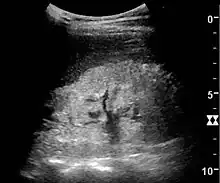

Kidney ultrasonography is useful for diagnostic and prognostic purposes in chronic kidney disease. Whether the underlying pathologic change is glomerular sclerosis, tubular atrophy, interstitial fibrosis, or inflammation, the result is often increased echogenicity of the cortex. The echogenicity of the kidney should be related to the echogenicity of either the liver or the spleen (Figure 22 and Figure 23). Moreover, decreased kidney size and cortical thinning are also often seen and especially when disease progresses (Figure 24 and Figure 25). However, kidney size correlates to height, and short persons tend to have small kidneys; thus, kidney size as the only parameter is not reliable.[54]

Nephrotic syndrome. Hyperechoic kidney without demarcation of cortex and medulla.[54]